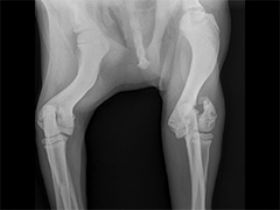

שבר מורכב של מפרק ברך אצל כלב